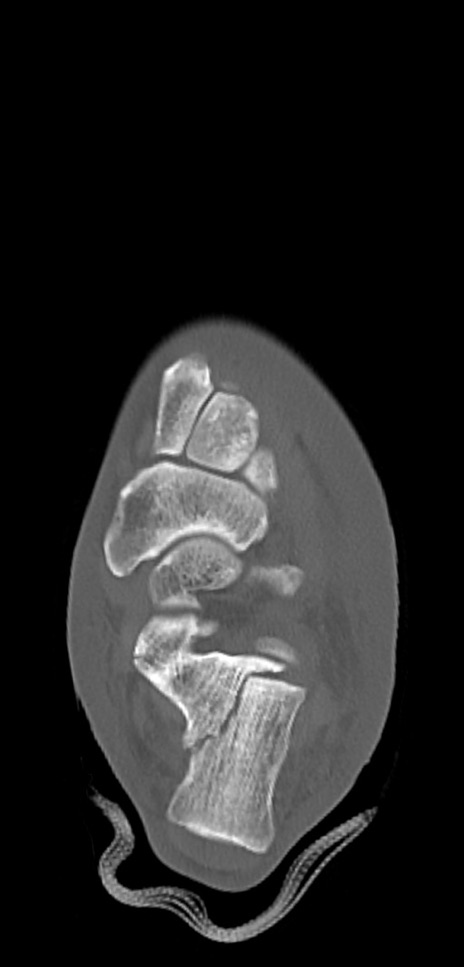

左足関節CT

冠状断像